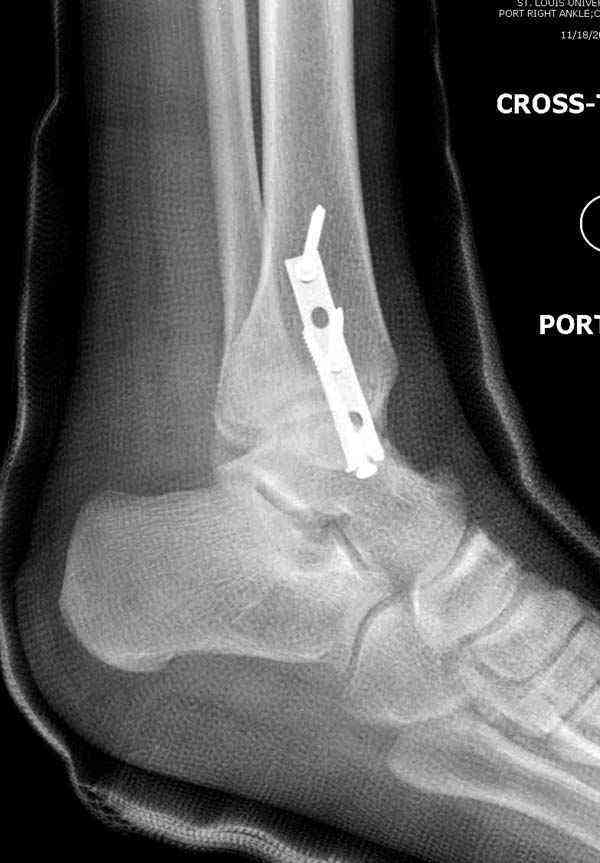

Достаточно быстрое восстановление функции.В октябре 2009г-почувствовала боль,в области рубца над гайкой открылся свищ.На Р-граммах-консолидация переломов и смещение гайки по стяжке.10.11.2009г-конструкции удалены,санация,заживление ран.В настоящее время пациентку ничего не беспокоит.На операции-раскручивание гайки-болталась на конце стяжки.Вопросы:какой механизм раскручивания и что я неправильно сделал?Свои версии:1)в области синдесмоза успела образоваться рубцовая ткань,которая при движении в суставе"пружинила",поскольку голеностопный сустав является спиральным, то и биомеханика подобна кривошипному механизму.2)Реконструктивная пластина не "реконструировалась" по форме лодыжки.Наложил,как есть.То есть подпружинивала сама пластина.Ну,это мои догадки.Что нужно,чтобы избегать впредь таких,пусть и не "страшных"осложнений:Рассверливать через лодыжку область синдесмоза?Ставить шайбу-гровер?Тщательно моделировать пластину?Прилагаю сравнительные снимки-сразу после операции и перед удалением конструкции.

Визуально никаких вопросов по репозиции не было.Да и на основании чего сомнения,что наружная лодыжка не полностью репонирована или прорезалась проволка ???Я не вижу...Снимок после репозиции справа.

Реконструкционные пластины на лодыжке очень грубые, и из-за тонкого слоя кожи над дистальным концом малоберцовой могут осложниться пролежнями кожи изнутри.

Нет первичных снимков, перелом очень низкий и под большим сомнением диагноз разрыва синдесмоза. Медиальная сторона отрепонирована на "хорошо" и, по-видимому, прорезание проволоки произошло во время операции. Без снимков трудно судить о высоте малоберцовой, а лодыжка находится в варусе. Лагирование получилось, но возле тонких шурупов передне-задний шуруп выглядит немного тяжеловато.

Во всех руководствах АО имеется описание техники применения низкопрофильных пластин 1/3 трубки, которые могут быть применены для фиксации наружной лодыжки. Фиксацию проводят кортикальными 3.5 мм шурупами, и если дистальная фиксация недостаточная, тогда усиливают конструкцию созданием hook plate. Сгибая конец пластины на последнем отверстии, внедряют его в дистальный отдел, и тем самым создается дополнительная фиксация.

Здесь несколько частных случаев: перелом голеностопа со сравнительными снимками и разрыв синдесмоза, а также медиальная Hook пластина.